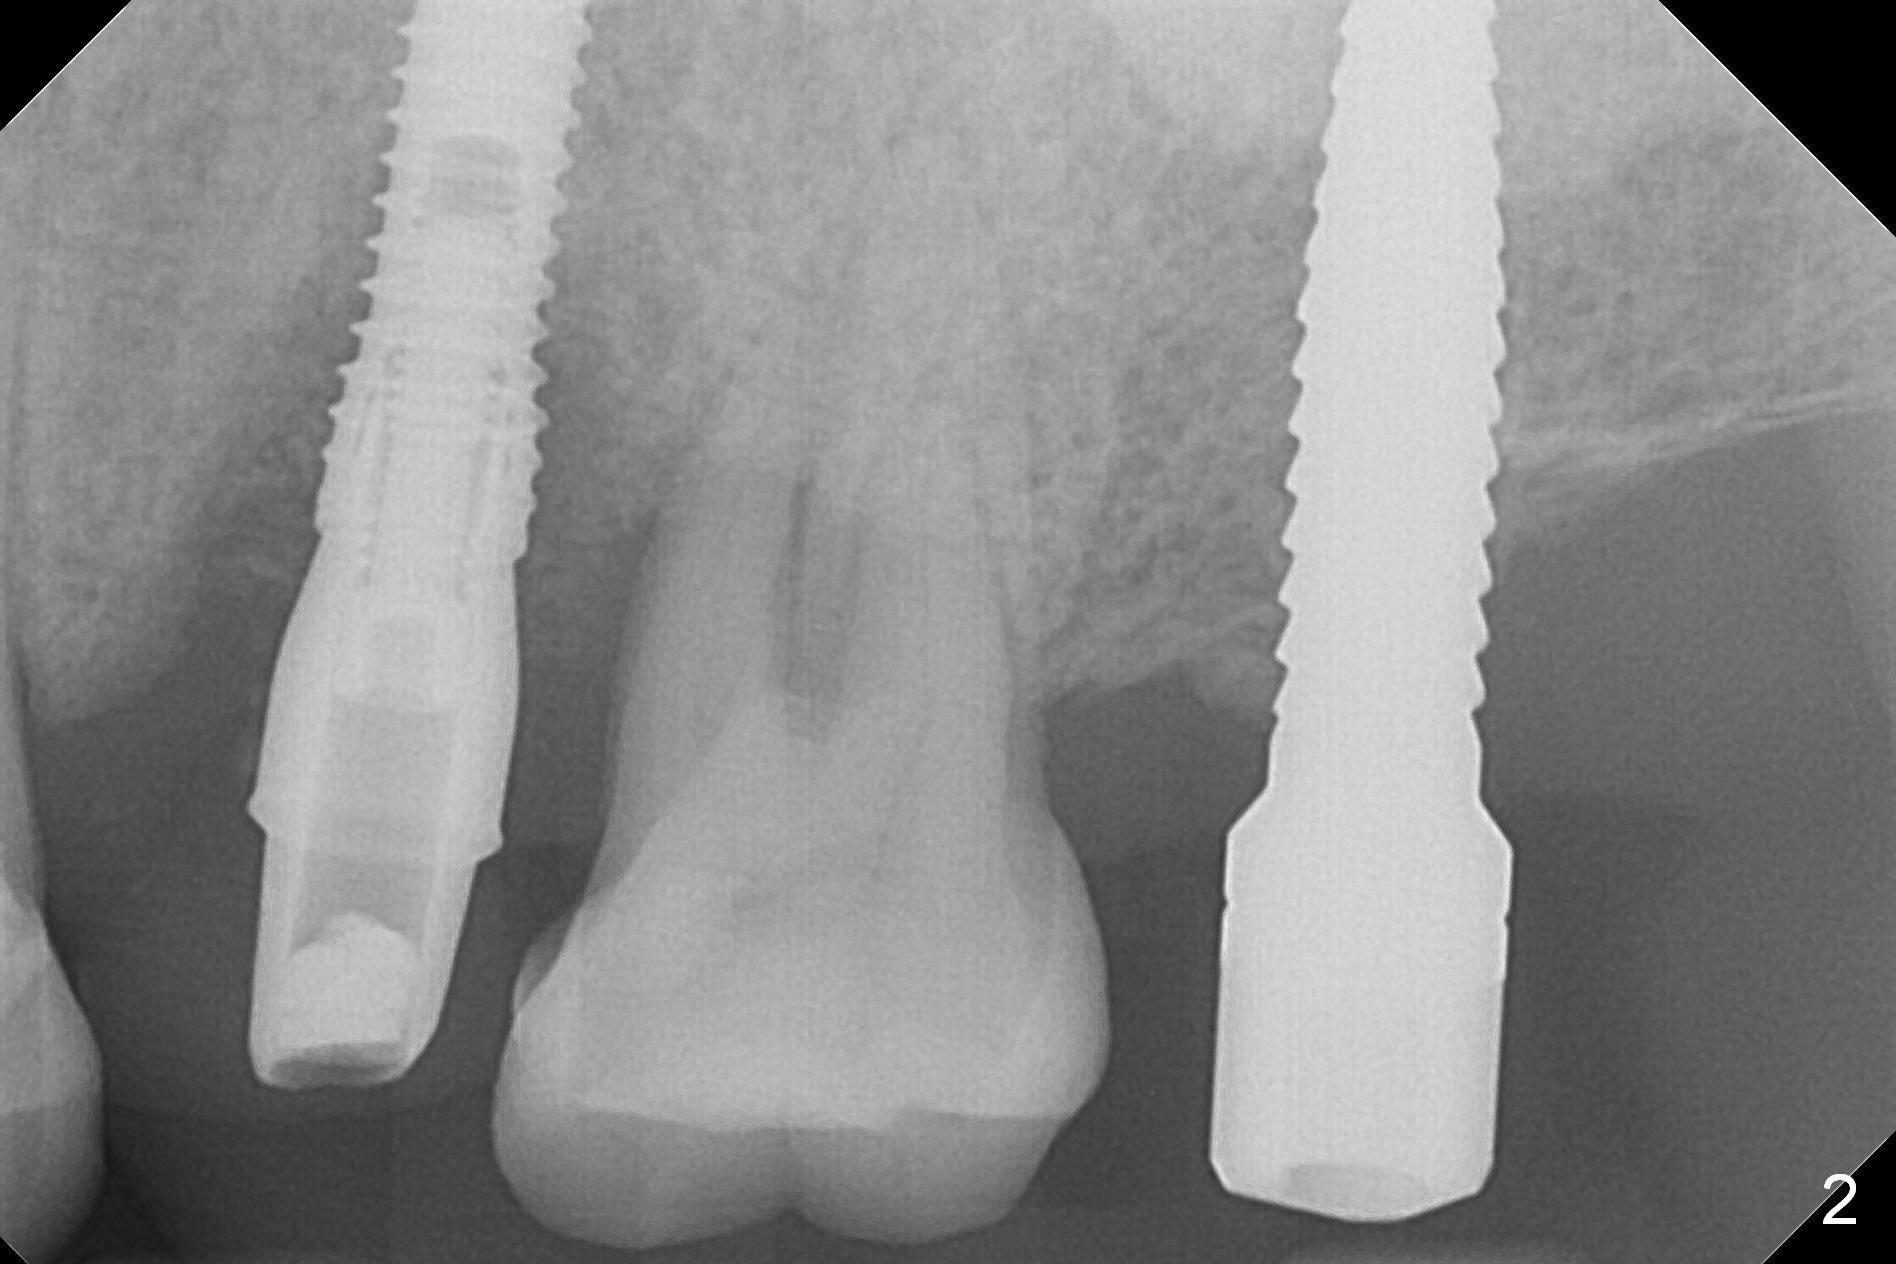

A 1.2 mm initial drill is used to start osteotomy at the site of #15 (Fig.1). After moving the osteotomy distally (with Lindamann bur), the osteotomy is enlarged by DIO Bone Expanders until 2.4/3.7 mm for 18 mm (gingival level) (Fig.2). Following the expander 3.0/4.4 mm, a 5x13 mm UF implant is placed supracrestal (Fig.3,4). After deepening the osteotomy with 3.8 mm drill for 3 mm, the implant is placed deeper by ~ 2 mm (Fig.5 arrow). Since the tooth #18 is supraerupted, a healing abutment (5.5x12(3) mm) is placed (Fig.6: H); the gingiva adapts to the abutment well. Suture is not necessary. The bone remains stable 2 and 4.5 months postop (Fig.7,8). Impression is taken. A crown is delivered nearly 6 months postop (08/07/2017). While there is minimal bone loss at #13 and 15 three years and 4 months post cementation, the tooth #14 and 18 are mobile (Fig.13,14, #13).